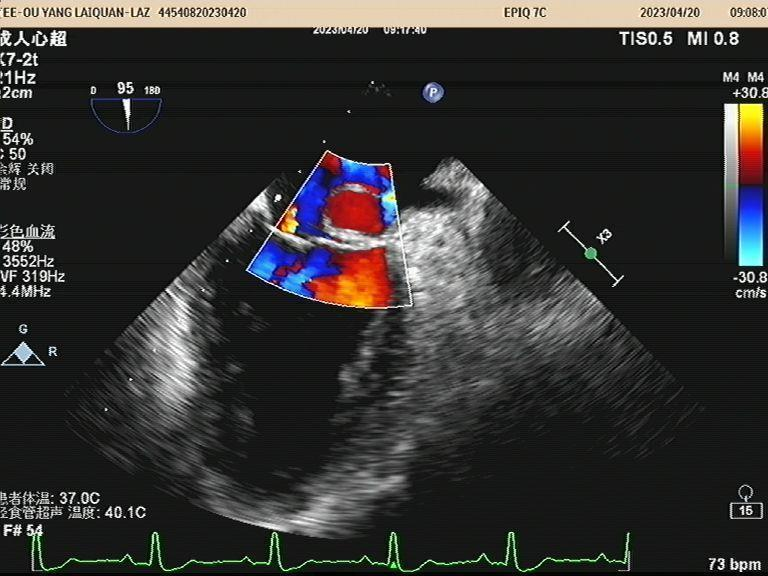

高洪波介绍,经食管超声心动图(TEE)是将超声探头置入食管内,从心脏的后方向前近距离探查其深部结构,可以实时观察心脏的结构、形态,并对心脏血流动力学情况和心功能状态做出合理评价。该方法避免了胸壁、肺气等因素的干扰,故可显示出清晰的图像,提高对心血管疾病诊断的敏感性和可靠性,是经胸超声心动图(TTE)的有效补充。

经食管超声心动图主要用于经胸超声检查显像困难或部分结构显示不满意的患者,诊断难以明确的心脏或大血管疾病患者,包括各类心血管畸形、心脏瓣膜病、 感染性心内膜炎、主动脉疾病、心脏占位性病变、冠状动脉疾病,也可应用于人工瓣膜功能评价及肺静脉血流的观察与检测。